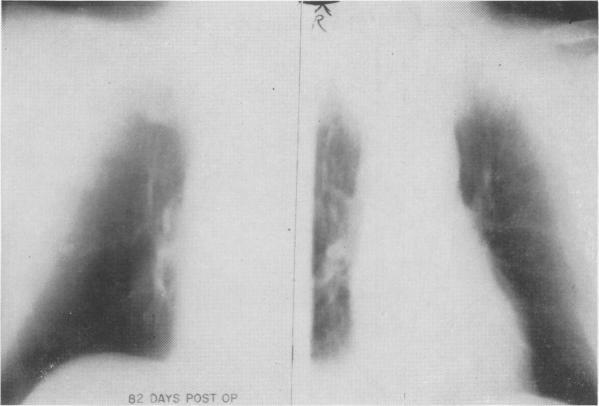

A gastric factor in the pathogenesis of the Zollinger-Ellison syndrome.

Ann Surg. 1968 Sep;168(3):483-501. doi: 10.1097/00000658-196809000-00015.